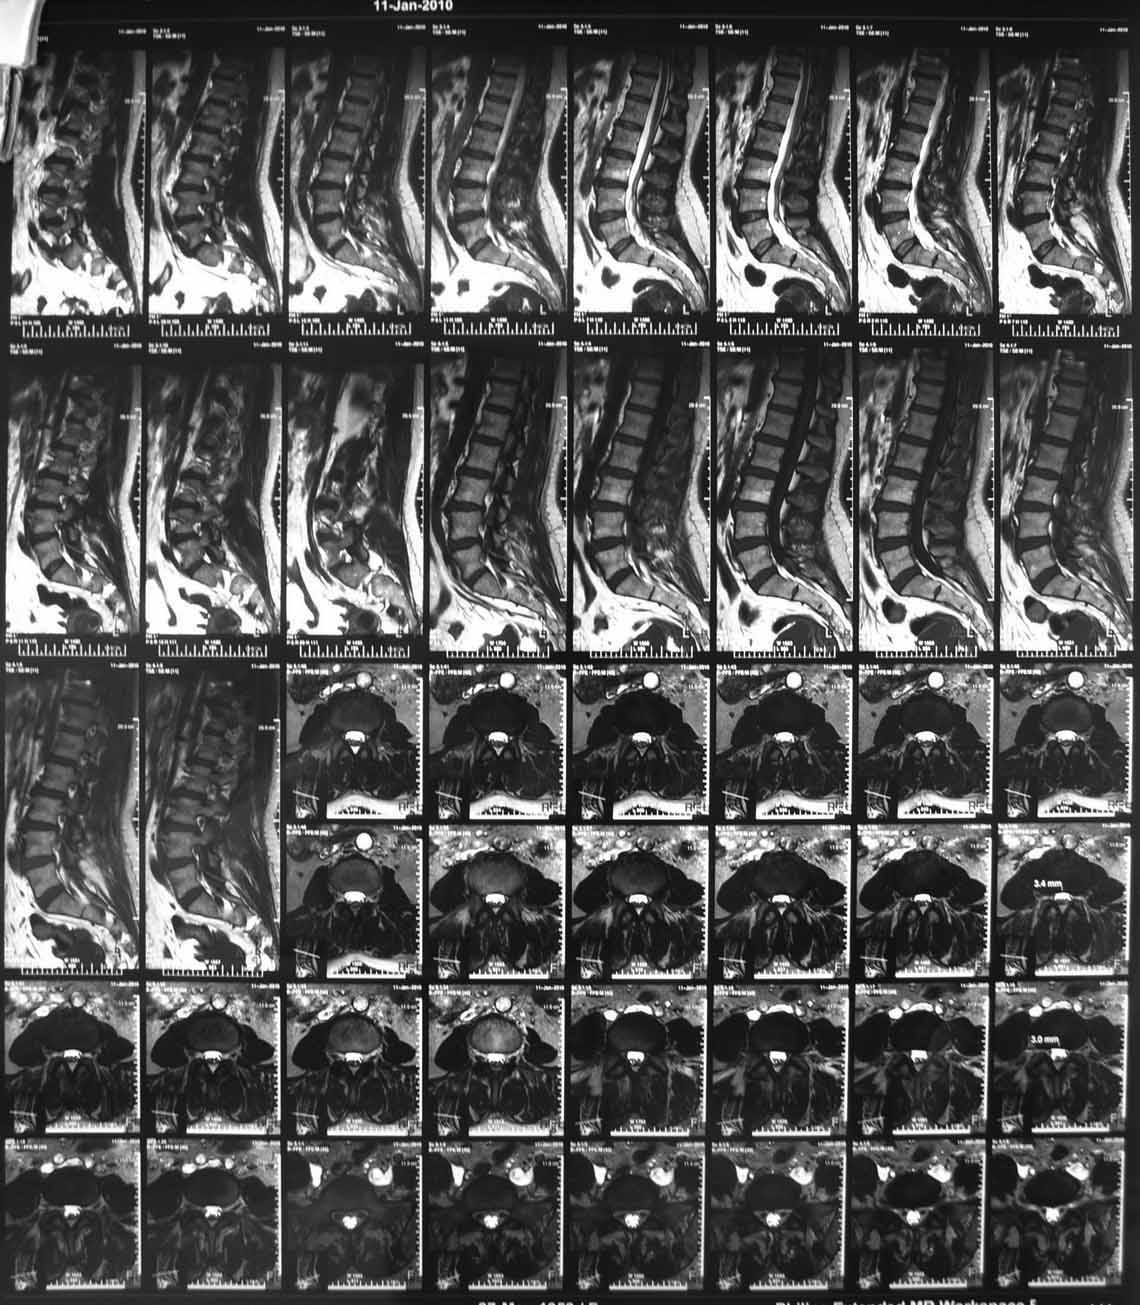

Боли отмечала и раньше, но они беспокоили не сильно, справлялась мазями, отдыхом. В течени последних пяти лет боли выраженного характера, не зависящие от положения тела, усиливающиеся при движениях, при резких движениях и кашле стреляющего характера, не иррадиирую. Ходит с трудом при помощи костылей. Движения ограничены из за боязни боли. Сиптомы натяжения отрицательны. Последние 3 года на инвалидности (была врачем). Неоднократно проходила курсы консервативного лечения по поводу остеохондроза позвоночника (сосудистые препараты, НПВС, всевозможные блокады, массаж)санаторно-куротное лечение с незначительным и очень ограниченным эффектом. На Р-граммах, КТ, МРТ остеохондроз не выраженный, грыж дисков нет. Лечилась у неврологов, консультирована вертебролагами в разных НИИТО.

На первичных КТ от 19-12-2009 определяется частичное анкилозирование правого крестцово-подвздошного сочленения, а на последних, от 11-04-2011 протяженность анкилозированной зоны значительно больше - сакроилеит прогрессирует, (с левой стороны вроде тоже признаки сакроилеита появились - не очень понятно из-за качества снимка). Значимых дуральных и радикулярных конфликтов действительно нет. "расслоение кости" - рентгенологически выглядит как травматический перелом подвздошной кости. Что делать? - наверное, искать серонегативные спондилоартропатии у ревматолога.